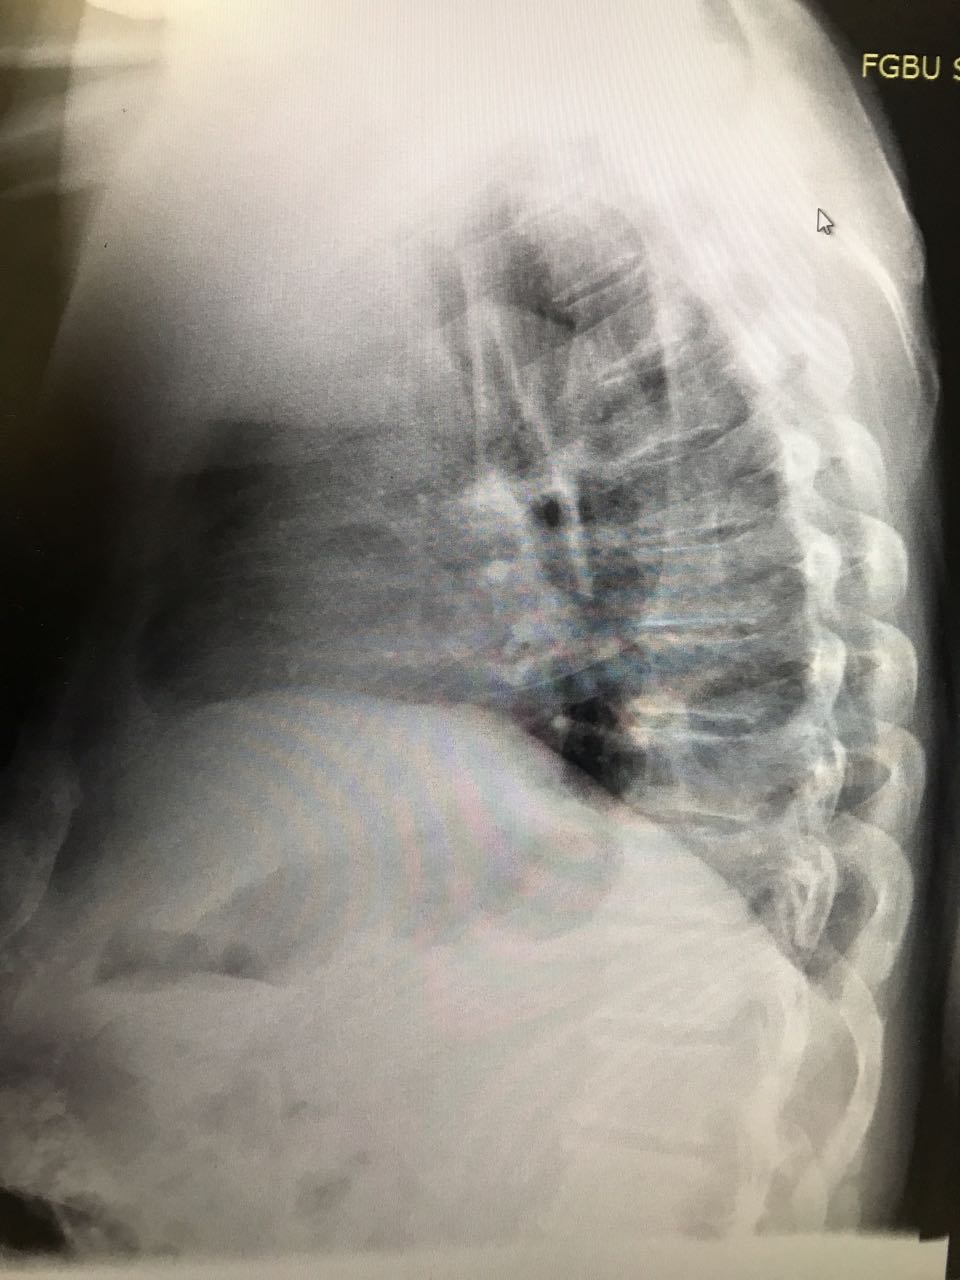

На рентгене гиповентиляция - признак центрального рака

Обсуждалось в Госпитале Ослабленных Сердец

Рак преимущественно левого легкого

Центральный рак. Ателектаз слева.